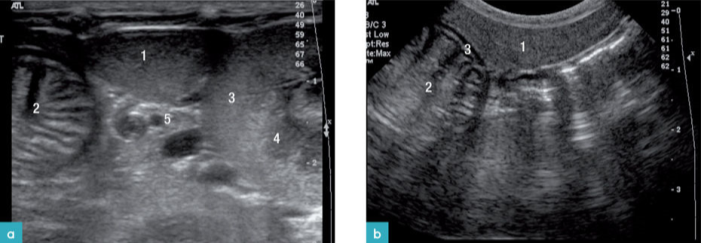

脾脏位于左侧上腹部,靠近胃底部、左肾头极与左侧腹壁(图1)。脾脏有两个表面:体壁面与脏器面。体壁面朝向左侧腹壁,表面凸起。脏器面(又称肠系膜面)朝向内侧,脾门在长轴上将脾脏分成两个部分(图2)。

健康动物的脾脏边界清晰,被膜薄而光滑(图2和图3)。脾脏的脏器面的轮廓不规则,是因为在脾门的地方有血管进出。横断面上的脾脏呈三角形(图4)。二维超声图像上很难看到脾动脉进入脾脏,需要使用彩色多普勒才能识别脾动脉(图3)。